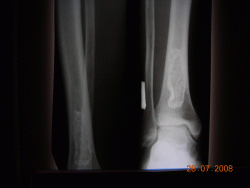

Здравствуйте коллеги. Я молодой врач рентгенолог, работаю первый год, после интернатуры, единственным рентгенологом в ЦРБ. Выскажите, пожалуйста, свое мнение по данному случаю.

Пациент, мужчина 50 лет, находился на обследовании и лечении в обл. центре по поводу ревматоидного артрозо-артрита правого голеностопного с-ва. Произведены сравнительные рентгенограммы обоих голеностопных суставов и случайно выявлены изменения в костях левой голени. Со стороны левой нижней конечности никаких жалоб не предъявляет. В выписке описания снимков нет, заключение: "Деформирующая остеодистрофия?"

Какой патологии, по вашему мнению, могут соответствовать изменеия в левой б/берцовой кости, аналогичная картина в н/трети левого бедра.

Позволю себе не согласиться с мнением уважаемого коллеги. На представленных рентгенограммах фрагментов левой голени (верхней и нижней 1/2) в проксимальном и дистальном метадиафизах б/берцовой кости отмечаются эксцентрично расположенные, ориентированные вдоль кости участки деструкции костной ткани неоднородной ячеистой структуры, достаточно четко отграниченные от окружающей ткани склеротическим ободком, слегка деформирующие (едва заметно вздувающие) кость на уровне поражения. Кортикальный слой сохранен, периостальной реакции, гиперостозов нет. Эта картина соответствует фиброзной дисплазии. Мелореостоз характеризуется чаще всего практически однородным, "стелющимся" эксцентрично вдоль длинной оси кости склерозом в виде слегка волнистой полосы, переходящим через линию суставов на другие кости. Корковый слой изменяется всегда, утолщаясь при этом как в сторону к/м канала (эндостально), так и наружу (периостально). При этом поверхность кости приобретает волнистые, местами гребневидные "оплывающие" контуры (стекающая свеча). Склертические полосы могут быть прерывистыми и расслоенными, но ячеистый рисунок для этого процесса не характерен.

Искала мелореостоз, наткнулась на эту ветку... Должна разочаровать, Валентин Львович, здесь обызвествленные интрамедулярные инфаркты, а не мелореостоз

Конечно, инфаркты, другого не дано.